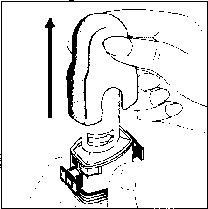

1. Kapağı çekip çıkarınız

2. Kapsül bölmesini açınız.

İnhalerin tabanını sıkıca tutup, açmak için ağızlığı üzerinde yer alan ok işareti yönünde döndürünüz.

3. Parmaklarınızın tamamen kuru olduğundan emin olunuz. Blisterden bir kapsül çıkarınız ve bu kapsülü cihazın tabanındaki kapsül bölmesine yatık olarak yerleştiriniz. Kapsülü, kullanmadan hemen önce blisterden çıkarmanız önemlidir.

ÖNEMLİ: Kapsülü ağızlığın İçerisinekoymayınız!

4. “Tık” sesini duyana kadar ağızlığı ok yönünün tersine döndürerek kapsül bölmesini kapatınız.

5. Tozu kapsülden serbestlemek için:

Not: Kapsül bu aşamada parçalanabilir ve küçük jelatin parçacıkları ağzınıza ya da boğazınıza gelebilir. Fakat jelatin yenilebilir nitelikte olduğu için zararlı değildir._ 6. Nefesinizi dışarıya olabildiğince veriniz.

- Kenarlardaki iki kulakçığa (düğmelere) aynı anda ve sadece bir kez sıkıca basarak kapsülü deliniz.